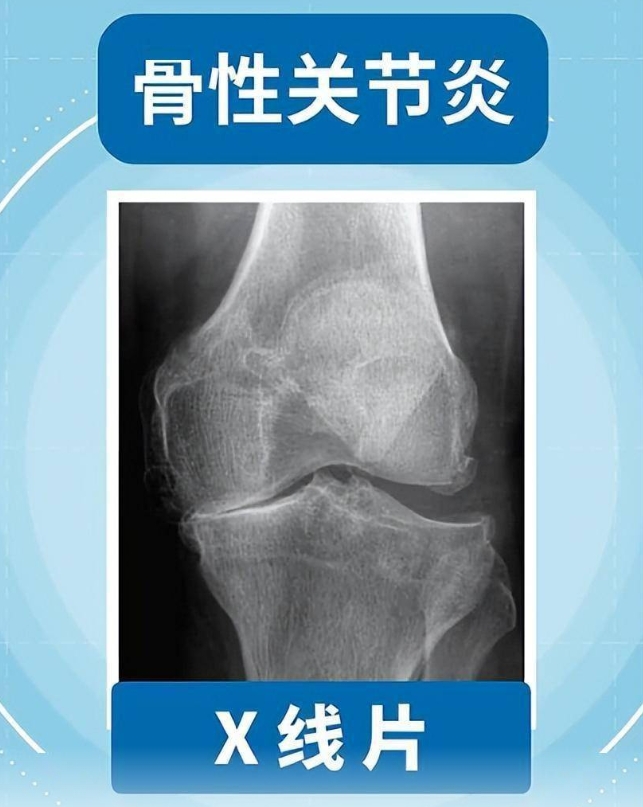

新浪新闻客户端:且行且珍“膝”!膝盖脆弱的你,请收好这份护“膝”秘籍